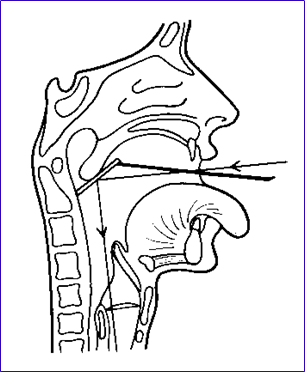

第一位置:受检头位稍低以观察鼻腔底、下鼻甲、下鼻道、鼻中隔前下部及总鼻道的下段。

第二位置:受检者头部后仰至30。检查鼻中隔中段及中鼻甲、中鼻道和嗅沟的一部分。

第三位置:头后仰至约60。,可看到鼻中隔上部、中鼻甲前端、鼻丘、嗅沟和中鼻道的前部。

镜面向前向上:可见软腭的背面,鼻中隔后缘、后鼻孔、各鼻道及鼻甲的后段、鼻咽顶部;镜面向左向右转动:见咽鼓管咽口,咽鼓管隆突、咽隐窝等结构。

检查中注意鼻咽粘膜有无充血、粗糙、出血、浸润、溃疡、脓液、新生物及鼻咽两侧是否对称,以便早期发现鼻咽癌。